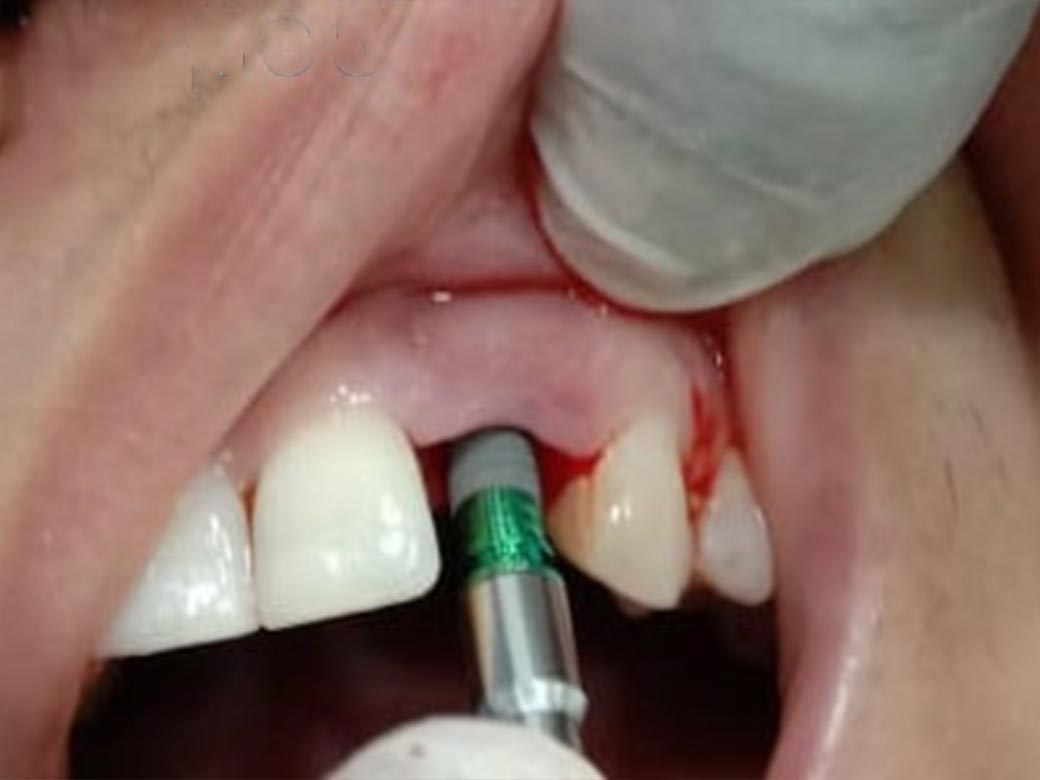

Step : CBCT was taken in our centre. Reports showed only root piece left inside the tooth socket. So, treatment was planned. In her case scenario the plan was to remove the left out root piece followed by implant placement & immediate capping.

Step 1 : X-ray taken.

Step 2 : Root piece removed under LA without pain.

Step 3 : Implant measurement compared with root piece.

Step 4 : Implant placement was done in the same socket.